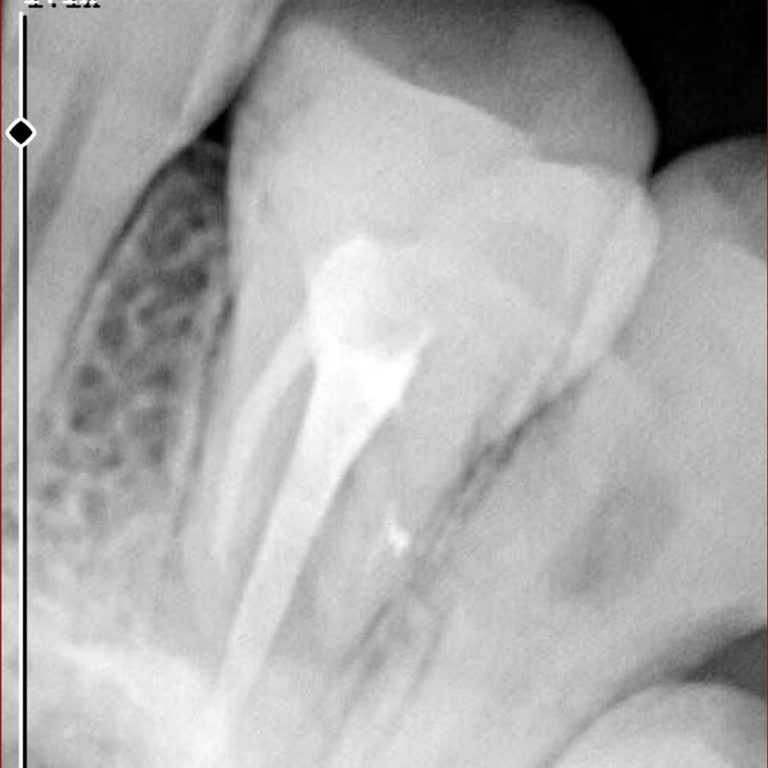

Alanya özel baha sağlıkta kanal tedavisi olmuştum kanal tedavimde üç sinirin sadece bir tanesini doldurmuş diğer iki tanesini yapmamış ve benim iki yıldır dişim ağrıyordu, bunu yapan bir diş hekimi olamaz adı ****** **** denilen şahsiyet 'görmemişim' diye başından savması bu işte ne kadar yetersiz o...